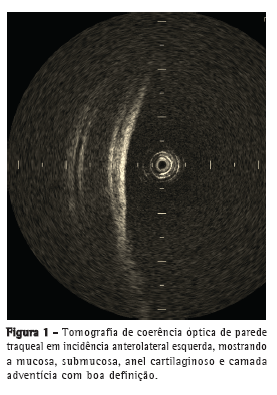

A OCT foi capaz de delinear, em tempo real, microestruturas, tais como epitélio, submucosa, cartilagem e camada adventícia (Figura 1) das paredes anteriores e laterais da traqueia de forma semelhante às imagens histológicas (Figura 2). Na parede posterior, as camadas correspondentes à mucosa, submucosa e musculatura traqueal foram claramente diferenciadas na OCT (Figura 3) e condizentes com a imagem histológica (Figura 4).